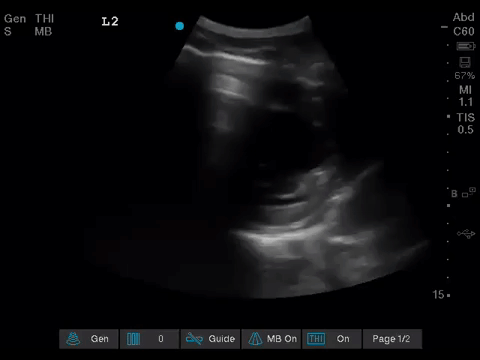

The POCUS team was asked to specifically to assess her lungs to help determine the cause of her dramatically increased oxygen requirements.

Before giving their clinical interpretation of the LUS findings, the POCUS team also scanned the heart and vasculature to obtain a more complete picture.

1. When scanning the lungs, a comprehensive, bilateral lung scan is far superior to a single clip; as this will offer more information and permit an interpretation based on the overall pattern of findings. Had this patient only had the R1 area scanned, for example, we may have reached the erroneous conclusion that her hypoxemia was likely due to pulmonary edema.